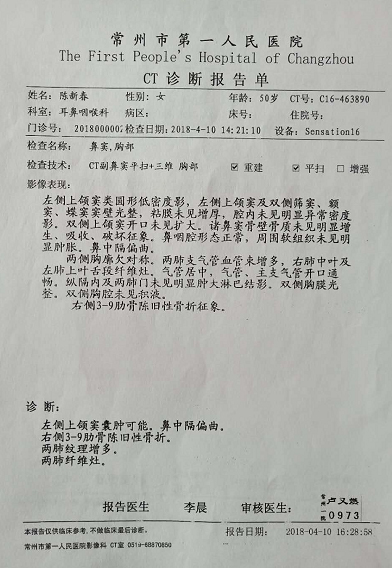

我叫陈新春,女,1968年3月出生,小学文化程度,江苏省盐城市射阳县人。2017年11月3日,在江苏省常州市新北区文化广场工地,八号楼二楼清理施工垃圾。因安全措施不到位,从6米高空施工洞坠入,造成颈椎骨折,脊柱骨折,腰椎L1一6横突骨折,腰椎右侧横突骨折,右侧髋臼,股骨头骨折装钢板,盆骨右侧L1一5骨折,左侧L1一5骨折,双侧耻骨折,左侧髋臼可疑骨折,腰椎至骨盆除左侧髋臼可疑骨折,全部骨折,外阴跌撕,胸椎骨折,内骨粉质性骨折,内骨右侧横突L1一4骨折,内骨左侧3一7两处骨折,右侧肋骨L1一10骨折,右侧肋骨后缘3一7两处骨折,左侧肋骨1.2.3.5.6.7.10骨折,后缘肩往下1一4两处骨折,左肩袖损伤肌健骨折;左冈上肌损伤,左肱骨因血液不流通,左肱骨长一个小圆形囊肿,腹部闭合性损伤,全身多处软组织损伤;双侧微量气胸,肝挫伤出血,脾挫伤出血,左肾挫伤出血,右肾上泉挫伤伴血肿,右肺上叶及两肺下叶挫伤出血,内腹部都挫伤出血。

现在尿蛋白阳性1十,肌酐比值阳性2十,肌酐比阳性2十,一直吃激素药,两肺纤维化吃阿四匹林肠容片维持,脾胃功能下降,慢性浅表性胃炎伴局灶糜烂,血管肉瘤,脂肪肝,团块。经常疼痛,经常咳血,便血,大便困难,小便失禁,因颈椎骨折压迫神经,导致细网膜委缩,电脑验光0.001都没有。

这里所提供的几张片子拍出的颈椎骨折,腰椎横突骨,脊柱骨折,左侧盆骨骨折,内骨粉质性骨折,内骨左侧3一7两处骨折胸椎骨折,报告单都没有。报告单上有50根骨折包括两处有的,只出三分之一的骨折。常州市武进人民医院涉嫌隐瞒我的伤情,进手术室开刀涉嫌隐瞒了主要骨折的片子,去要片子不给;补出院小结,补两次,颈椎骨折,腰椎骨折,胸椎骨折,内骨粉质性骨折还不肯补。